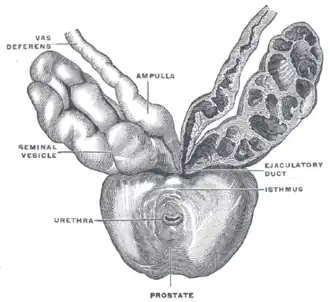

Próstata com vesículas seminais e ductos seminais, vistas de frente e por baixo.

A classificação de "lóbulo" descreve lóbulos que, embora originalmente definidos no feto, também são visíveis na anatomia macroscópica, incluindo dissecção e quando visualizados endoscopicamente.[4][3] Os cinco lóbulos são o anterior ou istmo, o posterior, os laterais direito e esquerdo e o médio ou mediano.[8]

Lóbulos da próstata

Lóbulos da próstata -